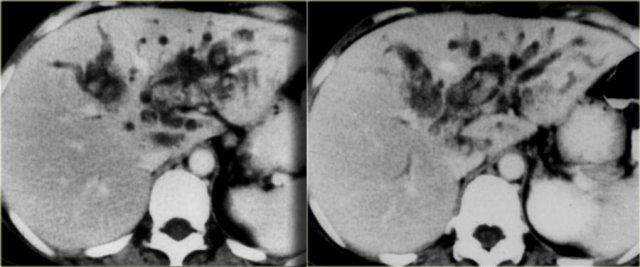

Các dấu hiệu CT giai đoạn muộn được thấy trong các hình ảnh bên trái.

Hãy quan sát các hình ảnh rồi tiếp tục đọc.

Các dấu hiệu bao gồm:

- Thay đổi hình thái xơ gan (mất thể tích thùy phải và thùy đuôi to ra (mũi tên))

- Giãn đường mật rõ hơn

Chụp đường mật được sử dụng trong chẩn đoán ban đầu của bệnh khi chỉ có các chỗ hẹp tinh tế, và ở những bệnh nhân đã biết mắc PSC để tìm kiếm các chỗ hẹp mới nghi ngờ ung thư.

Trên hình ảnh chụp đường mật, chúng ta có thể thấy:

- Hình chuỗi hạt (Beading): hình ảnh xen kẽ giữa các chỗ hẹp và các đoạn ống mật bình thường hoặc giãn nhẹ

- Hình cây trụi lá (Pruned-tree): các ống mật ngoại vi bị hẹp và khó quan sát

- Bờ thành không đều (Mural irregularity): bờ lòng ống không đều (thấy rõ nhất ở bên trái trong ống mật ngoài gan)

- Túi thừa (Diverticula): thấy rõ nhất ở bệnh nhân tiếp theo

Bên trái là các dấu hiệu điển hình trong PSC.

Lưu ý các túi thừa trong hình bên phải.

Túi thừa có tính đặc hiệu rất cao cho chẩn đoán PSC.

Vì vậy, khi phát hiện các túi thừa này, bạn cần tìm kiếm ngay các chỗ hẹp tinh tế ở các ống mật trong gan.